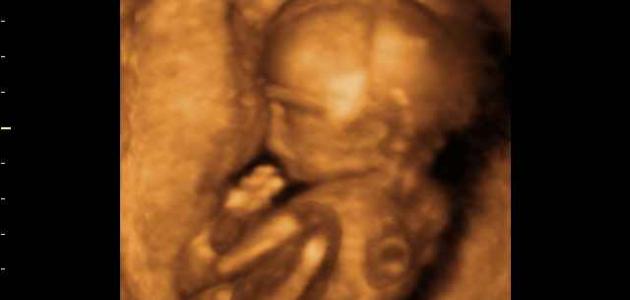

تعتبر فترة الحمل من أجمل الفترات التي تمّر فيها المرأة في حياتها، على الرغم من جميع الصعوبات والمشاكل سواء الصحيّة أو النفسية التي تتعرض لها المرأة، وتطرأ على المرأة في كلّ مرحلة من هذه المراحل مجموعة من التغيرات وتحديداً الجسدية؛ نتيجةً لتغيرات الهرمونات الجسدية عندها، وبالتالي تظهر عليه مجموعة من الأعراض والعلامات المختلفة في كل مرحلة؛ لذلك سوف نتناول هنا أبرز الأعراض التي تظهر على الحامل خلال الأسبوع الخامس تحديداً من حملها، وكيف يمكن مواجهتها وتخطيها.

إنّ جميع التغييرات التي تظهر على المرأة خلال أشهر حملها تكون بهدف مساعدة الجنين على النمو والتطور بشكل طبيعي، وخلال الأسبوع الخامس من الحمل تطرأ على الحامل مجموعة أعراض وتغيّرات ومن أبرزها ما يلي: